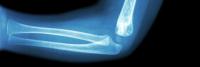

If your child needs diagnostic imaging for an illness or injury, you want fast, accurate results. You want a convenient location with a modern, comfortable setting. And you want to work with friendly experts you can trust.

- X-ray (all ages)